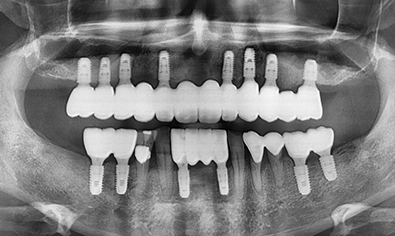

빠르고 정교하게!

바쁜 현대인을 위한

원데이 임플란트

환자가 원한다면 발치 즉시 임플란트를 식립하여

잇몸뼈 소실을 줄일 수 있습니다.

임플란트 식립, 임시 보철물 제작까지

단 하루만에 가능합니다.

원데이 임플란트가

가능한 이유!

대학병원 수준의 디지털 장비 보유

트리오스 구강 스캐너 프라임스캔 구강 스캐너 3D 프린터 및 밀링 기계 사용하여 당일 보철을 제작합니다.

원내 가이드 직접 제작

원장이 직접 수술용 가이드를 제작하여 수술 당일 보철의 적합도를 증가 시킵니다.